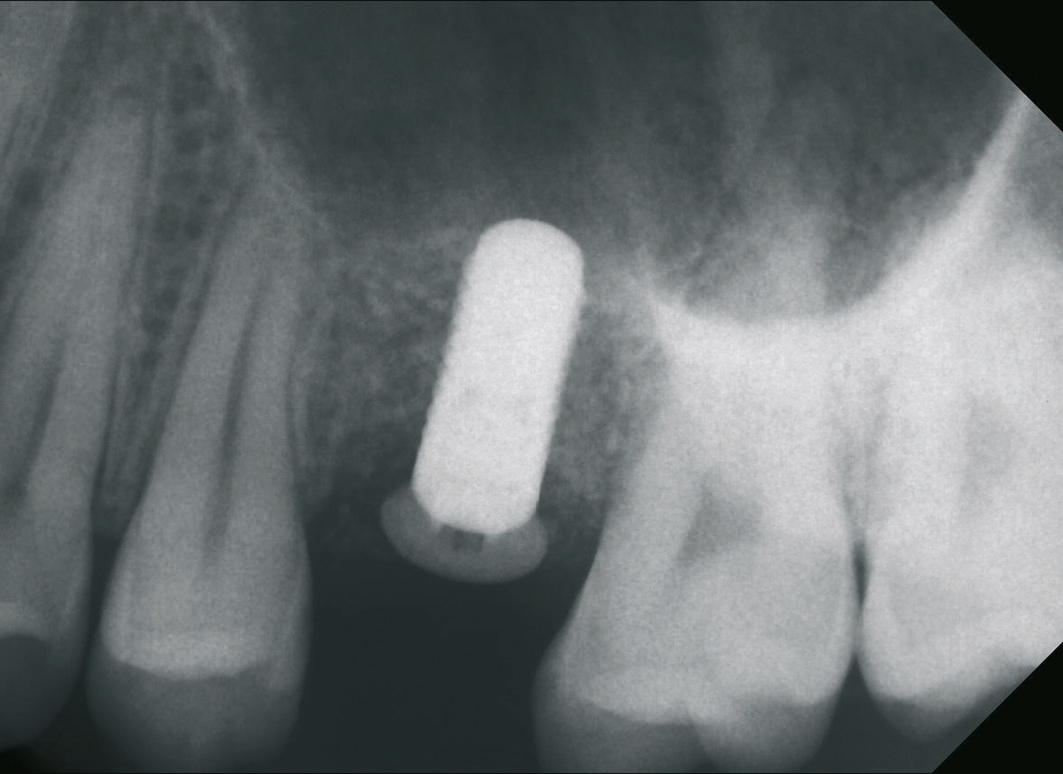

Ein 21-jähriger Patient stellte sich mit einer Perkussionsempfindlichkeit in regio 26 vor. Die klinische Untersuchung zeigte einen tiefzerstörten Zahn 26, dessen gesamte palatinale Wand tief fraktruiert war. Die Frakturgrenze verlief dabei weit unter dem palatinalen Zahnfleischrand (Abb. 1). Nach Erstellung eines Orthopantomogramms und einer radiologischen Einzelzahnbildaufnahme war eine längliche Verschattung am Apex der palatinalen Wurzel des Zahn 26 zu erkennen (Abb. 2), die den Verdacht einer überinstrumentierten Wurzelkanalaufbereitung der palatinalen Wurzel und einer Überstopfung des Füllmaterials bestätigte (Abb. 3). Nach konservierender Theapie wurde die Indikationsstellung für die Extraktion des Zahnes 26 mit einer Sofortimplantation gestellt. Der Periodontal-Screening-Index wies in allen Sextanten Grad 2 auf. Es folgte die Erstellung einer dreidimensionalen Röntgenaufnahme (Orthophos XG 3D, Dentsply Sirona, Bensheim) zur virtuellen Planung der Implantatposition. Die operative Planung erfolgte in der Planungssoftware coDiagnostiX 9.5 (dental wings, Montreal, Kanada) (Abb. 4).

Nach der Präparation des Weichgewebes wurde ein Mukoperiostlappen mit Hilfe der Instrumentenspitze PR2 (Piezosurgery, Mectron, I-Genua) vorsichtig präpariert, um eine suffiziente Deckung der Wunde zu gewährleisten (Abb. 9 und 10). Nach Vorbereitung des Weichgewebes wurde die 3D-gedruckte Bohrschablone auf den Zahnbogen gesetzt und ein Führungsschlüssel mit 2 mm Durchmesser eingesetzt, durch den ein Osteotom einführt wurde, um eine Führung für den nachfolgenden Trepanbohrer in den Knochen kondensierend zu präparieren (Abb. 11). Entlang des Führungskanals wurde das Bett für den allogenen Knochenring (maxgraft bonering; botiss biomaterials GmbH, Berlin) trepaniert (Abb. 12). Der allogene Knochenring wurde extraoral passgenau zugeschnitten und anschließend in die Extrationsalveole platziert (Abb. 13 und 14). Mittels eines breiten Osteotoms wurde der Knochenring samt basalem Knochensegment schablonengestützt nach apikal in den Sinus maxillaris verschoben. Ein parallelwandiges Implantat (Bone Level Roxolid, SLActive, Straumann) mit einem Durchmesser von 4,1 mm und einer Länge von 10 mm wurde zentral in den positionsstabilen Knochenring primärstabil inseriert, mit einer Fixierungkappe (Durchmesser 5,5 mm) versehen und die umliegende Extrationsalveole mit granulärem bovinem Knochenersatzmaterial ausgefüllt (Abb. 15-17). Anschließend wurde die Wunde mit dem Mukoperiostallappen gedeckt und speicheldicht vernäht (Abb. 18). Zur postoperativen Kontrolle wurde ein Orthopantomogramm aufgenommen, auf dem keinerlei Verletzungen benachbarter anatomischer Strukturen zu erkennen sind (Abb. 19). Es folgten zwei radiologische Verlaufskontrollen, vier und sechs Monate nach dem Eingriff, ohne Besonderheiten (Abb. 20 und 21).